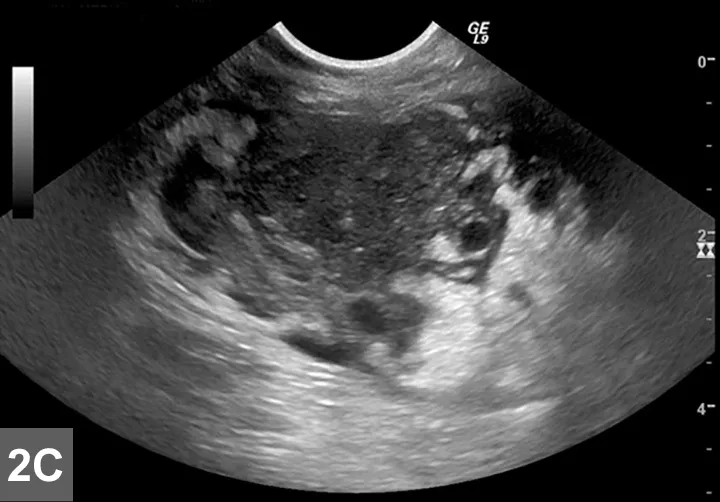

FIGURE 2A

Cranial mediastinal mass in a cat. Note the increased opacity of the entire cranial mediastinum with border effacement of the cranial margin of the heart and dorsal deviation of the trachea in the lateral view.

Mediastinal

• Typically localized form of LSA involves infiltration of the thymus and/or cranial mediastinal and sternal lymph nodes with intermediate to large neoplastic lymphocytes with signs related to the intrathoracic mass effect and secondary pleural effusion (Figure 2).